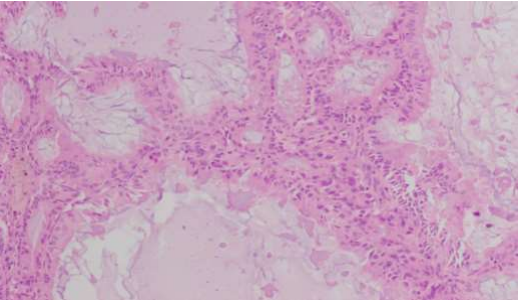

H and E images showing endometrial glands crowded and superficial invasion of myometrium

H and E images showing endometroid carcinoma with central mucin present.